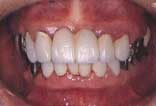

| 初診時 口腔内写真 | 1か月後 | 2年後 | 投薬後1か月 |

| 歯肉の腫脹が著しい 64歳・女性 |

徹底的に歯石除去したけれど… | メインテナンスの甲斐なく歯肉腫脹 | 歯肉状態大幅に改善 |

口腔内およびX線所見:

年齢の割には残存歯牙数が多く、歯槽骨の吸収はやや少なめではあるが、口腔清掃状態が

不良で歯肉の腫脹が著しい。歯肉縁下歯石も予想に反してやや少なめであった。

処置および経過:

歯周疾患初期治療と平行して、主訴である上顎前歯部の補綴処置を進めた。スケーリング→

スケーリング&ルートプレーニングおよび根面処理を行ったにも関わらず期待する程の歯肉改善

が見られなかったが、臼歯部の咬合支持確保の必要性から、メインテナンスによる改善をあてに

して見切り発車的な形で歯冠補綴を進めた。